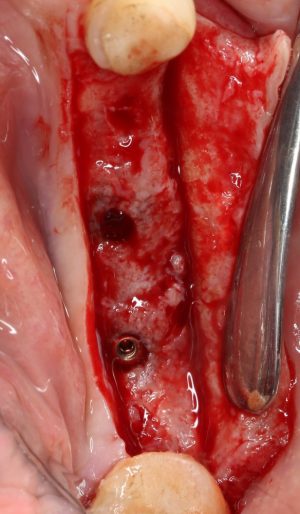

Для удаления зубов мы используем прямой элеватор и тонкие «корневые» щипцы-байонеты. Сама процедура удаления занимает около 10 минут:

Давайте внимательно посмотрим на состояние лунок центральных резцов после удаления:

Приемлемый фенотип (сочетание толщины и ширины участка жевательной десны) — это, конечно, приятно. Но гораздо важнее сосредоточиться на рисках, их на этот момент два:

— травматическое повреждение слизистой, вызванное удаление зубов связано с тем, что при хроническом воспалении слизистая оболочка теряет эластичность, поэтому легко рвётся. Такая ситуация создаёт серьёзную угрозу эстетическому результату лечения, в зависимости от того, насколько быстро десна придёт в норму.

— как и предполагалось после КЛКТ, утрата костной стенки привела к тому, что десна провалилась в просвет лунки левого центрального резца. Это еще больше усугубляет клиническую ситуацию.